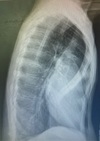

61

Homem, 15 anos, dor em região dorsal. Febre + tratamento para endocardite.

Espondilodiscite Redução do espaço discal, irregularidades dos platôs vertebrais adjacentes.